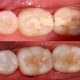

عدم رعایت بهداشت دهان و دندان به مرور زمان منجر به رشد باکتری ها در اطراف دندان ها و لثه های شما میشود که طبیعتاً نتیجه فعالیت آنها عفونت دندان و در نهایت آبسه دندان است. اما به طور کلی نحوه این اتفاق به نوع آبسه هم بستگی دارد:

- آبسه پری اپیکال: در این حالت باکتری ها از طریق پوسیدگی وارد دندان های شما می شوند و پالپ و قسمت های نرم داخلی دندان را تحت تاثیر خود قرار می دهند. این قسمت از دندان حاوی اعصاب و رگهای خونی است و به راحتی آسیب می بیند.